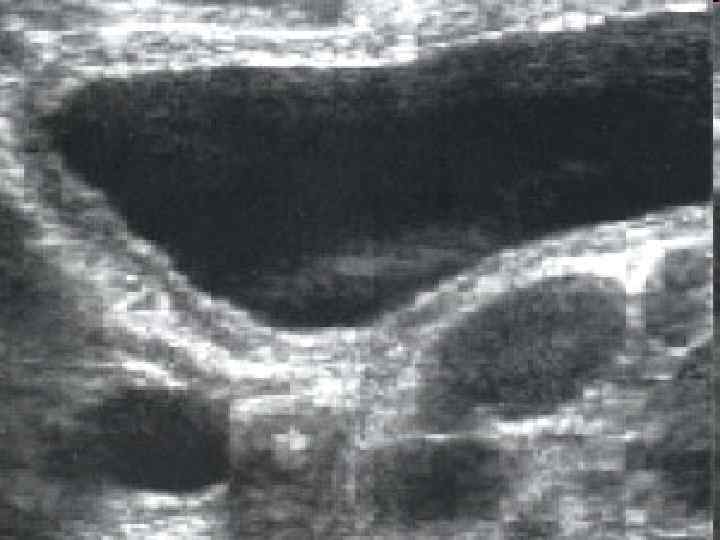

Острый холецистит • Локализация боли в правом верхнем отделе живота • Иррадиация в правое плечо и лопатку • Тошнота и многократная рвота с симптомами раздражения брюшины или без таковых. • Положительны симптомы Грекова-Ортнера, Образцова, Кера и др. • Лейкоцитоз со сдвигом формулы влево и увеличение СОЭ. • Наиболее надежным и доступным диагностическим приемом в данной ситуации является ультразвуковое исследование.

УЗИ желчного пузыря при остром холецистите. Выявляется растянутый желчный пузырь (толстая стрелка) с камнем, вколоченным в устье пузырного протока (тонкая стрелка), отбрасывающим акустическую тень. Стенка желчного пузыря значительно утолщена.

Ультразвуковыми признаками острого холецистита являются • • • утолщение стенок желчного пузыря более 4 мм "двойной контур" стенки увеличение размеров желчного пузыря перивезикальной жидкости положительный УЗ-признак Мерфи (локальное напряжение желчного пузыря под УЗ-датчиком). • По данным УЗИ можно судить о форме воспаления желчного пузыря